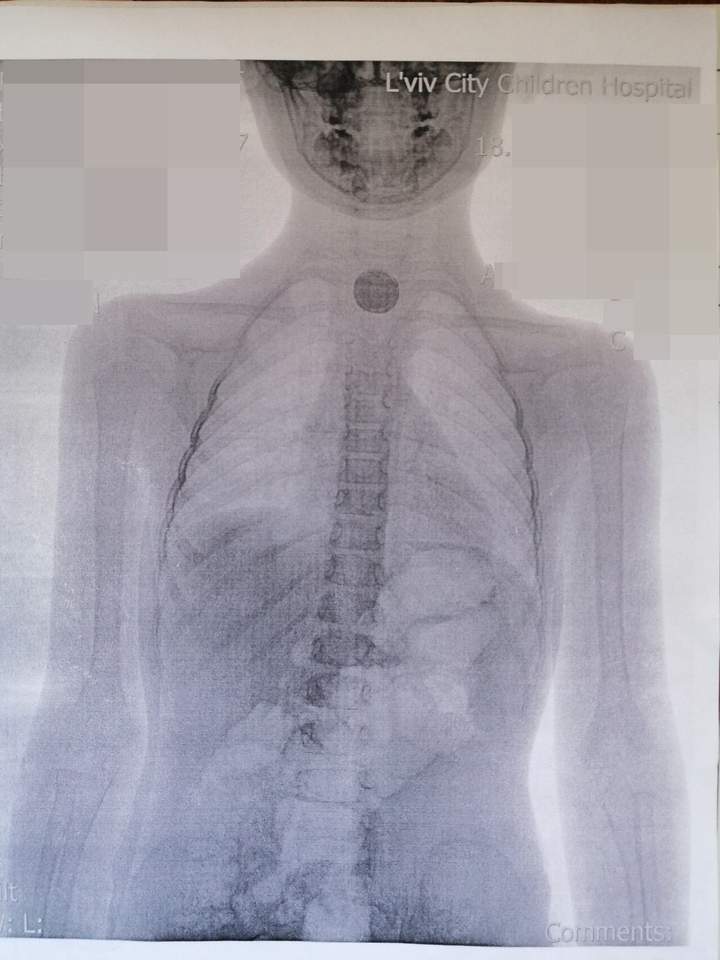

"Во львовской городской детской больнице девочке сделали рентген и направили со снимком к нам, в ОХМАТДЕТ. На снимке видно в пищеводе инородное тело круглой формы. 11 июля мы прооперировали девочку. Когда зашли в пищевод, то поняли, что она проглотила не монету, а батарейку: там было все черное и обожженное", - рассказал детский хирург Александр Колодий.

Хирурги вытащили батарейку, размером с монету 25 копеек из пищевода девочки. Она спровоцировала у ребенка сильный отек и ожог пищевода. Через 3-4 недели станет ясно, не образовались ли рубцы на месте ожога. Если это произойдет - ребенок будет нуждаться в длительном и непростом лечении.